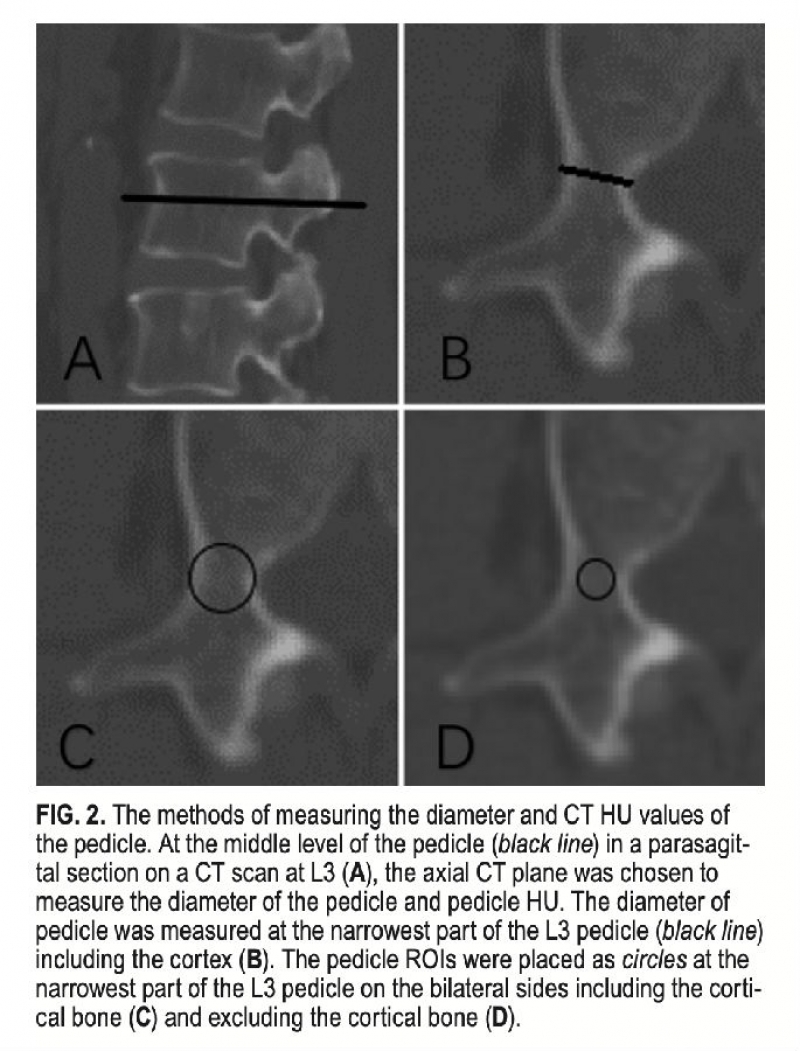

材料与方法:回顾性分析143例因腰椎退行性疾病接受L3-5后路减压融合内固定术的患者资料。依据术后1年L3椎弓根螺钉的状态将患者分为螺钉松动组和非螺钉松动组,利用术前腰椎CT测量L3椎体CT值和L3双侧椎弓根CT值均值。

结果:术后1年L3椎弓根螺钉松动率20.3%。椎体CT值和椎弓根CT值的Pearson相关系数约为0.4(P<0.001)。螺钉松动组的椎体CT值,不包括皮质骨的椎弓根CT值,包括皮质骨的椎弓根CT值均低于对照组(P<0.001)。包括皮质骨的椎弓根CT值预测螺钉松动的AUC值大于椎体CT值的AUC值,但差异没有统计学意义(P>0.05)。在L3椎体CT值≤130HU的患者中,椎弓根CT值>340HU 的患者螺钉松动率远小于椎弓根CT值≤340HU的患者(13.0%vs.31.0%,P<0.05)。

结论:椎弓根CT值与椎体CT值线性相关,但相关性不大。部分患者虽然椎体CT值很低,但椎弓根CT值可能很高,其螺钉松动风险也相对较低。因此,同时测量椎弓根CT值和椎体CT值有助于提高螺钉松动预测准确性。

图注:椎弓根CT值测量示意图